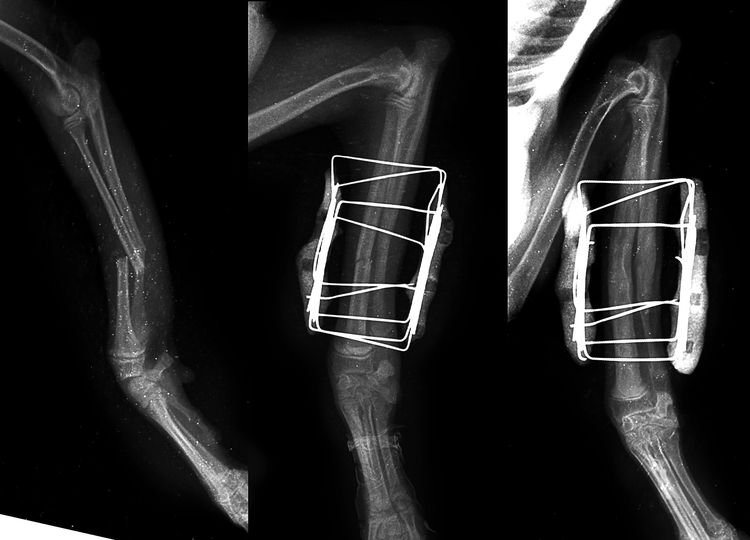

La plupart des fractures des membres chez le chien (environ 90 %) nécessitent une intervention chirurgicale. L'ostéosynthèse (fusion osseuse) est réalisée à l'aide de broches, d'agrafes, de vis et de plaques. Ces dernières années, grâce aux progrès technologiques, les vétérinaires utilisent désormais des dispositifs en polymère, en plus des dispositifs métalliques.

- L'appareil de Kishner. Une structure composée d'une tige métallique et de tiges autotaraudeuses est utilisée pour les fractures intra-articulaires.

- L'appareil d'Ilizarov se compose de broches et d'anneaux métalliques qui maintiennent fermement en place les fragments d'os.

- Fixation interne. Intervention la plus complexe. Le chirurgien doit posséder les qualifications et l'expérience nécessaires pour la réaliser efficacement. Des broches sont insérées directement dans les os longs. Elles ne sont pas retirées et restent en place à vie.